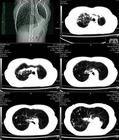

1、X線檢查:一側肺不發育在X線胸片上見患側胸腔密度均勻緻密,其內缺乏充氣的肺組織以及支氣管影和血管紋理的痕跡,心臟和縱隔結構均移向患側,患側的橫膈面顯示不清,對側正常肺呈不同程度的代償性肺氣腫,以致橫膈下降,膈面變平,過度膨脹的肺可形成縱隔疝。如果同時見到脊椎有半椎體畸形則很有助於診斷。另一部分肺發育不全可在X線胸片上顯示肺組織充氣,但肺紋理稀少,相比之下有時會被誤認為是健側支氣管炎症或支氣管擴張,須特別注意。

2、支氣管造影:可以顯示患側主支氣管缺如,氣管似乎直接與另一側主支氣管相連線,或主支氣管呈發育不良畸形,或支氣管分支的數目稀少。行肺血管造影檢查可見患側肺動脈主幹發育不良或缺如,有助於確定診斷。

3、肺動脈灌注掃描:患側顯示肺血流減少或明顯減少。